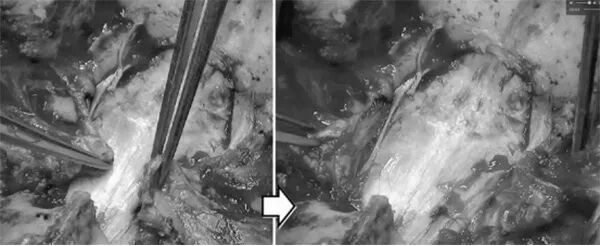

手术,经后路,在显微镜下分离颈1后弓、颈2棘突及椎板.

在颈1后弓外上显露并保护椎动脉,显露颈1侧块后弓,用直角探针探查确定颈1后弓基底内壁,确定后弓侧块螺钉入针点,用直径2mm克氏针,由入口内聚10度,电钻在后弓及颈1侧块做长22mm骨道,透视满意后,拧入直径3.5mm、长22mm颈椎椎弓根螺钉。由颈2椎板向外上显露颈2外科椎弓根头侧边缘,保护颈2神经根、勿损伤颈1,2椎弓根之间的硬膜外静脉丛。暴露硬膜侧缘,确定螺钉入针点,用直径2mm克氏针,由入口内聚6-7度,在颈2椎弓根内壁可视并保护情况下,电钻在后弓及颈2外科椎弓根24mm骨道,透视满意后,拧入直径3.5mm、长24mm颈椎椎弓根螺钉。